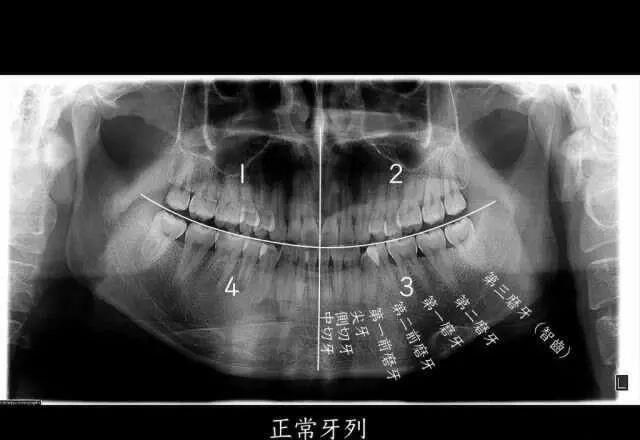

△智齿,也就是第三磨牙,位于口腔最远最深的位置。

如果我们把一个正常成年人的口腔分为左上、左下、右上、右下四个区域的话,每个区域会有8个牙齿,长在最后的第8颗牙齿,就是我们口中的“智齿”,也是我们的第三磨牙。